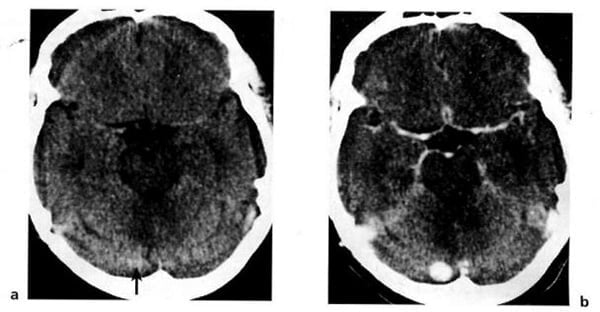

Hình 1.59. U màng ống nội tủy. Trước tiêm (a), không đồng nhất nằm ở vùng não thất 4 (mũi tên). Sau tiêm (b), bắt chất cản quang mạnh và không đồng nhất.

Hình 1.60. U nguyên bào mạch. Bệnh nhân nam 33 tuổi có hội chứng von Hippel-Lindau. Trước tiêm (a), tổn thương có mật độ hơi cao ở bán cầu tiểu não bên phải (mũi tên). Nốt u bắt mạnh chất cản quang (b).